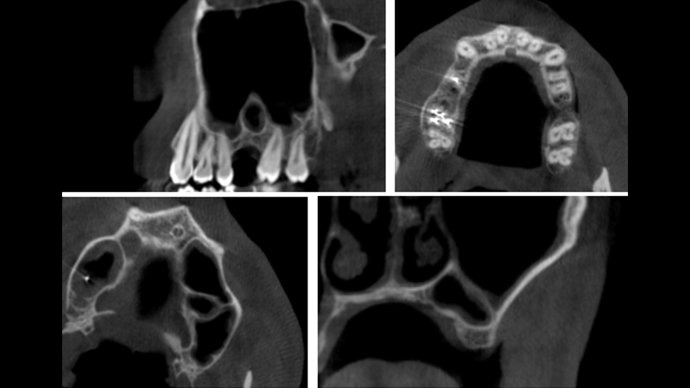

Clinical case: Delayed implant placement: sinus floor elevation by means of lateral

approach & implant placement with GBR

- Courtesy of Dr. Irfan Abas, Netherlands -